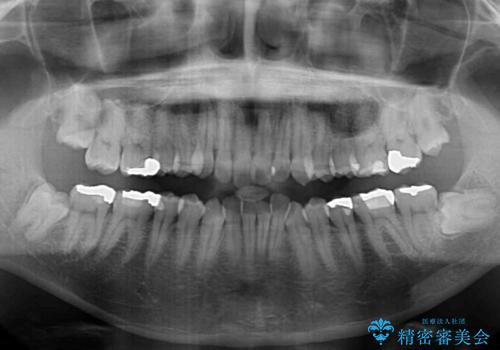

- 前歯のデコボコを気にして来院された患者様です。

下顎前歯のデコボコが特に強く、治療を早く終えることを考えるとワイヤー装置がお勧めですが、ワイヤー装置の異物感は避けたいのでインビザラインを希望されていました。

インビザラインで治療を行うか、ワイヤーで治療を行うかずっと悩んでいらっしゃいましたが、早く終わらせることを優先してワイヤー装置にて治療を行うこととしました。

下顎にワイヤー装置を装着し、暫くしたところでやはりインビザラインにて矯正治療をしたいとのことで、インビザラインに切り替えました。

短い期間でしたがワイヤー装置を使用したことでデコボコが解消されたため、インビザラインの比較的短い期間で矯正治療を行うことができました。